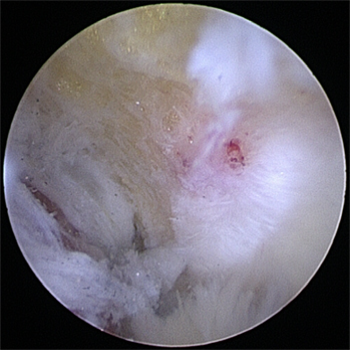

관절내시경을 통해 자라난 뼈 조각과 관절 내 유리체를 제거하며

자라난 골극을 제거해준 모습